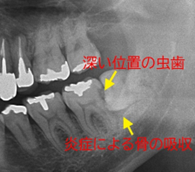

親知らずはまっすぐ生えてくれば大きく問題がないことも多いのですが、斜めに生えてきたり、歯茎に埋まっていたりしやすく、その場合虫歯や歯周病を引き起こす原因となることが多いため早目の抜歯をおすすめしています。

親知らずの抜歯、特に下あごでは、顎の血管や神経の走行によって抜歯が困難であったり、術後の出血やしびれなどのトラブルのリスクが高まることがあります。当院では歯科用3次元CTを撮影し、歯の正確な位置関係を把握してより正確な診断を行うことが可能です。